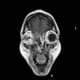

Paranasal sinusitis

Sinusitis, also known as rhinosinusitis, is inflammation of the mucous membranes that line the sinuses resulting in symptoms that may include thick nasal mucus, a plugged nose, and facial pain. Other signs and symptoms may include fever, headaches, a poor sense of smell, sore throat, and a cough. [Source: Wikipedia ]